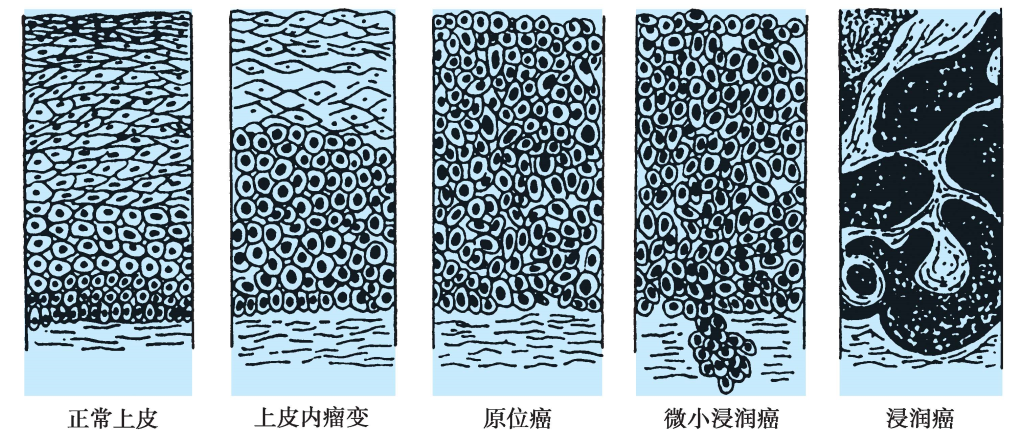

SIL形成后继续发展,突破上皮下基底膜,浸润间质,形成子宫颈浸润癌(图25-4)。

图25-4 子宫颈正常上皮-上皮内病变-浸润癌